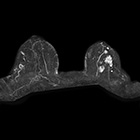

乳腺専用コイル

乳腺専用コイルでは、乳腺の精密検査の為の高分解能撮影を実現します。